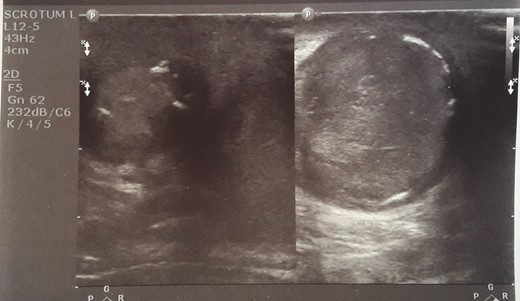

Initial sonographic findings were suggestive of epididymo-orchitis. The testis was well perfused and in normal position (Fig. 1). He was admitted for 3 days to start intravenous anti-inflammatory and antibiotic treatment and discharged under antibiotic treatment. Re-examinations were scheduled to assess treatment. On first reexamination, a week later, edema had subsided and the testis appeared hard, indurated and painless (Fig. 2). Ultrasound was still suggestive of epididymo-orchitis. Nevertheless suspicion for a testicular tumor was raised because of persistence of clinical and sonographic findings. An earlier appointment was scheduled this time. Five days later, at the second reexamination, another ultrasound showed reduced testicular perfusion that reached only the periphery of the testicular parenchyma (Fig. 3). The boy was operated as an emergency. Intraoperatively testis was non-twisted, with normal vas and vessels that ended in a necrotic testicular parenchyma. The testis was dark brown, hard on palpation and no blood came out when incised (Fig. 4). Right orchidectomy was performed. Since the exact cause of testicular necrosis was still unkown at the time of operation a left orchidopexy was performed to protect the only surviving testis from any future risk of torsion. The boy was discharged the next day. Histology showed a case of epididymitis nodosa and ruptured sperm granuloma that caused vascular compression, thrombosis and testicular necrosis (Fig. 5). More specifically, it showed proliferation of small ducts and gland-like structures in the walls of the vas deferens and epididymis in response to fluid and sperm dissection into the interstitium secondary to mechanical obstruction and increased intraluminal pressure. These findings are extremely rare in pediatric patients. The boy had an uneventful postoperative course and was discharged 2 days after surgery able to travel by sea to his home island.

Intraoperatively testis was non-twisted, with normal vas and vessels that ended in a necrotic testicular parenchyma.